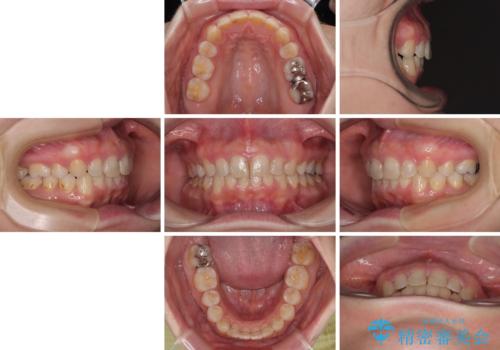

出っ歯を治したい ワイヤー装置での抜歯矯正

- 上の前歯が出っ歯と突出した口元を気にして来院された患者様です。

上顎歯列全体が前方に飛び出している印象であったので、上顎左右の第一小臼歯2本を抜歯し、ワイヤー装置にて抜歯矯正を行うこととしました。

骨格的に上顎が前方にあり、上顎のみの抜歯矯正のため、期間はかかることが予想されましたが、スムーズに移動してくれたおかげで、2年弱の短期間で終えることができました。